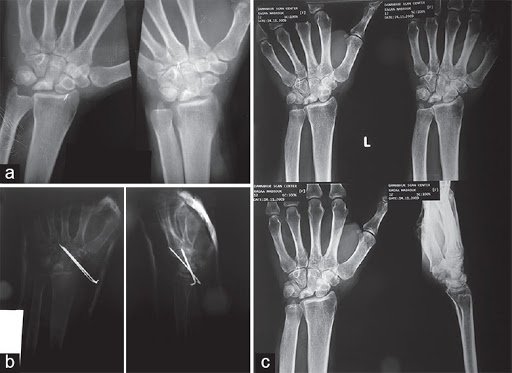

Morphologic Staging follows the Lichtman Classification, which is based on radiographic and MR imaging findings and has low interobserver variability.[rx][rx][rx]

Stage 1: Normal radiograph, lunate signal intensity changes on MRI.

Stage 2: Lunate sclerosis on radiography with or without fracture lines. The lunate shape is normal.

Stage 3: Collapse of the lunate articular surface.

- 3A: with preserved carpal alignment and height.

- 3B: with scaphoid flexion and loss of carpal height.

- 3C: with an associated coronal fracture

Stage 4: Stage 3B + radio-carpal or mid-carpal arthrosis.

- Radiography – Normal early in the disease. Findings, when present, depend on the morphological stage and include diffuse lunate sclerosis, cystic changes, articular surface collapse, carpal collapse, mid-carpal, and/or radio-carpal secondary arthrosis. Coronal fractures may occur in lunates with a type I morphology.[rx][rx]

- Computed Tomography – This is useful for surgical planning. It is also more sensitive than radiography for detecting subtle subchondral fractures, coronal lunate fractures, fragmentation, carpal instability, and the degree of trabecular disruption. Patients are frequently re-staged after CT imaging.[rx]